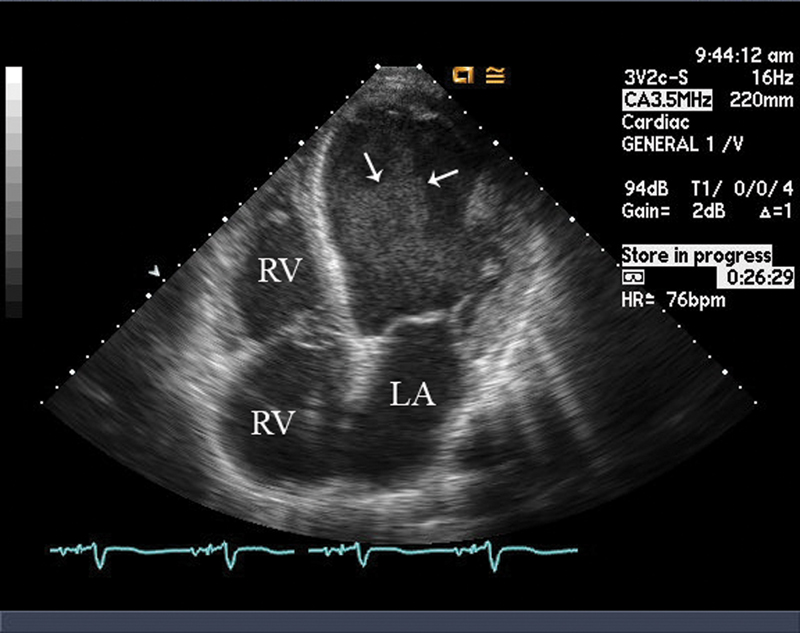

فحوصات تشخيصية لبعض امراض القلب والشرايين التاجية